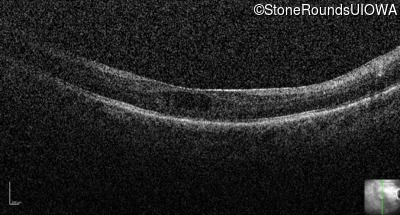

Optical Coherence Tomography - Right - 20/50 +2

Exemplar / OCT Stack

Optical Coherence Tomography - Left - 20/160